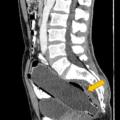

Ο άνδρας κατέληξε στο νοσοκομείο καθώς το μπουκάλι το οποίο ήταν σχεδόν 18 εκατοστών μπήκε κατά λάθος στον πρωκτό του.